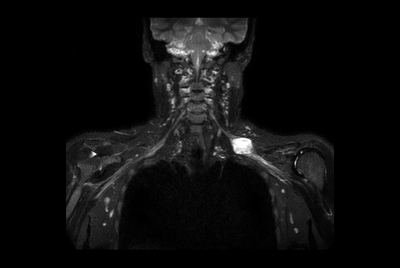

Brachial Plexus lesion